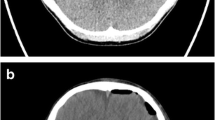

Lesion removal guidance

Extent of lesion removal was assessed with iUS in 152 procedures of neoplastic and non-neoplastic pathologies (except aneurysms and EVD placement) by acquiring repetitive iUS scan to compensate brain-shift as surgery proceeded (Fig. 4). As surgery proceeds, we have frequently observed a worsening of the iUS image quality due to surgical artifacts. Lesion removal was accurately checked in 127 patients out of 152. The phenomenon of echographic visibility reduction was not observed in cavernous hemangiomas, brain abscesses, AVMs, and extra-axial tumors (meningiomas, sellar region tumors, schwannomas); these pathologies remained easily visible throughout the operation with minimal or no decrease in iUS visibility. In these patients (48 tumors, 6 hemangiomas, 2 brain abscesses, 3 AVMs), quantification of extent of resection was possible as well as quantification of the potential residual (10 subtotal resection over 48 tumors).

Image quality was worse in the cases of intra-axial tumors (including metastasis); iUS tumor removal guidance was still considered useful, however, because iUS precision is better in excision quantification than the microscopic vision alone. Among 87 cases of intra-axial tumors, US removal control was possible in 68 patients. Forty underwent incomplete resection: 32 subtotal resection (STR) and 8 biopsies. Among 31 patients (25 STR, 6 biopsy), the residual lesion was identified and assessed, and the decision to not proceed further with the procedure was based either on anatomical criteria or the neurophysiological monitoring. In the remaining nine patients, iUS was not clear because of surgical artifacts (5 glioblastoma, 3 low-grade astrocytoma, 1 lymphoma). Forty-seven patients underwent gross total removal (GTR): HGG (29), LGG (5), metastasis (13). In 37 cases (21 HGG, 3 LGG, 13 metastasis), iUS visibility remained clear during the procedure and the system was considered helpful in tumor resection. In the remaining 10 cases, the images were not good enough and the excision was completed relying on microscopic vision and anatomical landmarks.

In our experience, a decrease in echographic visibility was encountered during intraparenchymal hematomas evacuation. The iUS was used to plan the transcortical trajectory, but in all six patients, we could not evaluate the progression of evacuation, with an average of one grade-lowering on the Mair classification. Power Doppler angiography was used to localize major vessels encased or adjacent to the lesion and major feeding arteries (tumors, AVMs). Displaying simultaneously iUS tissue signal and power Doppler allowed us to localize and spare vascular structures during both the approach and the resection (Fig. 5). Repeated intraoperative Doppler acquisitions were also used to check progressive deafferentation of AVMs and hypervascularized tumors. On the opposite of the tissue signal, we did not observe any decrease of the Doppler images’ quality throughout the procedure.

Final iUS evaluation of the surgical field

Resection control

The use of iUS for resection control during surgery of intracerebral tumors is documented in numerous reports; however, our aim was to assess iUS utility in all neurosurgical procedures and we therefore analyzed this application of iUS for non-neoplastic pathologies as well (cavernous hemangiomas, cerebral abscesses, hematomas). The ability to check the resection with ultrasound depends on the pathology’s echographic visibility both at the beginning and during surgery; it is common to observe a reduction of image quality during the procedure. Surgical artifacts can decrease the lesion’s US visibility and particularly the definition of its edges. We were able to accurately check resection in 127 cases out of 152 procedures (Table 2). In our experience, extra-axial pathologies (extra-axial tumors, cavernous hemangiomas, and AVMs) showed high visibility throughout the procedure with minimal decrease in image quality and high capacity of distinguishing borders from the surrounding cerebral tissue. Nevertheless, these are lesions in which the resection can be usually checked with microscopic view; therefore, iUS utility is limited to some specific cases. Echographic control during evacuation of cerebral abscesses, hematomas, or cystic lesions through a minimally invasive approach has been reported [8, 19, 21]. We used iUS with good results during evacuation of two cerebral abscesses and two cases of intraparenchymal hematomas (one associated with an aneurysm, the other with a cavernous hemangioma). In the remaining six hematomas, iUS resulted accurate to plan transcortical approach, but we could not check the evacuation due to low quality of US images. Solheim et al. in 2009 [15] proposed a method of ultrasound-guided resection of giant meningiomas (also effective with schwannomas and craniopharyngiomas): the method enables image-guided resection through narrow approaches that minimize traction on brain parenchyma. US tissue signal could be used to assess the amount of residual tumor (minimizing the risk of over- or underestimation of residual tumor), whereas power Doppler angiography allows the identification of normal arteries adjacent or encased in the tumor as well as feeding vessels [15]. We performed this kind of approach with satisfactory results in meningiomas, schwannomas, craniopharyngiomas, and AVMs (with control of progressive deafferentation with power Doppler).

One of the most used iUS applications is resection control of intra-axial tumors. The aim is to sonographically identify residual lesion which is not visible to the bare eye, in order to refine the resection. Several authors assessed the usefulness of this technique; however, randomized trials are still lacking. Woydt et al. [24] and Chacko et al. [1] compared 2D US imaging results after resection to histopathology by taking probes from various points at the resection margin. They concluded that iUS could detect residual tumor tissue with high specificity and thus improve gross total resection. The role of 3D ultrasound was widely studied by Trondheim’s group [12, 13, 16, 22]. Their studies show that ultrasound is highly accurate in delineating glioblastomas (and metastasis) before resection, but it appears less accurate during and after resection. During resection, there seem to be some overestimation of the tumor and on the contrary, small tumor remnants and infiltrated tissue in the cavity wall are underestimated after resection [12, 22]. In our study, a retrospective unselected population, we evaluated the utility of iUS (for resection control) based on the echographic visibility of the tumor throughout the procedure. On a total of 87 intraparenchymal tumors (HGG, LGG, metastasis, lymphoma), we could perform iUS-based resection control in 68 cases (37 GTR, 26 STR, 5 biopsies). We deemed useful in all cases, except from biopsies (in which quantification of residual tumor was not considered relevant). iUS allowed us to perform a direct control of resection. In the remaining 19 cases (10 GTR, 7 STR, 2 biopsy), image quality was inadequate to perform an accurate assessment of the resection. In the subgroup of giant intra-axial tumors, resection control could be difficult because of system’s inability to visualize the whole lesion together with its margins. This drawback could be overcome by alternating internal tumor debulking and US acquisitions until the borders become clear. Saeter et al. performed a retrospective analysis on the use of 3D ultrasound in 192 glioblastomas surgery. Their study demonstrated that survival rates improved within the same period that intraoperative ultrasound and neuronavigation were introduced and established in their department [13]; however, these findings are not confirmed by larger randomized controlled trial and the authors concluded that one must be cautious to claim causality between iUS and prolonged glioblastoma survival. In two comparative studies, 2DiUS resulted in slightly inferior to iMRI in resection control [3, 4]. Tronnier et al., however, showed that detection of HGG and metastasis and intraoperative delineation of tumor remnants through low-field iMRI (0.2 T) or 3DiUS was comparable in both imaging modalities whereas in the case of a low-grade glioma, iUS was more helpful [18]. Comparison between iUS and other intraoperative imaging (iCT or iMRI) is beyond the scope of this article; our aim was to assess the utility of routine use of iUS in intracranial surgery. Our study as well as literature data [1, 11,12,13, 16, 20, 22, 24] suggests that iUS has high sensitivity in detecting tumor remnants (higher than “bare eyes”) and hence could help improving gross total resection.